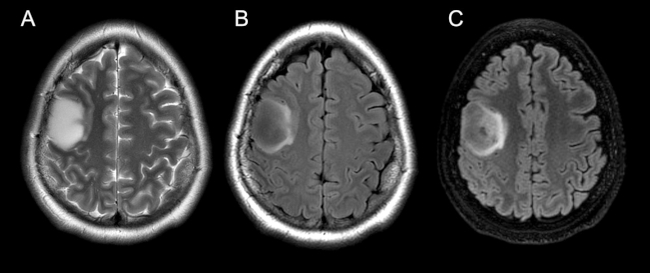

El signo del mismatch T2-FLAIR fue determinado subjetivamente como la completa o casi completa hiperintensidad de señal en secuencias ponderadas en T2 y marcada hipointensidad en FLAIR del área hiperintensa en secuencias ponderadas en T2, a excepción de un halo hiperintenso, visible en más del 50% del área tumoral (►Fig. 1). Para dicha valoración, se utilizaron como referencia estudios publicados respecto a la descripción del signo.7,8

En los últimos años, varios investigadores han estudiado la asociación entre las características morfológicas de los tumores por imágenes y su perfil de expresión genética que permiten predecir en cierto grado el subgrupo molecular. En particular, Patel y col.5, en el año 2017, describieron el signo del mismatch T2-FLAIR como la completa o casi completa hiperintensidad de señal en secuencia potenciada en T2 y señal hipointensa en secuencia FLAIR a excepción de un halo hiperintenso. Ese signo es uno de los más prometedores por su alto valor predictivo positivo (VPP), y considerado un biomarcador radiológico altamente especifico y con 100% de VPP en predecir la ausencia de la codeleción 1p/19q en gliomas IDH-mutados.7